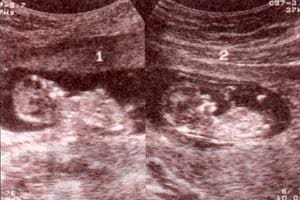

| fig. 53.– (a). gemelar bicorial – biamniótico. signo lambda. se establece precozmente el diagnóstico de corionicidad. en este caso se trata de un embarazo bicorial – biamniótico. | fig. 53.– (b). membrana interamniótica. obsérvese el grosor de la membrana correspondiente a un embarazo gemelar bicorial – biamniótico. |